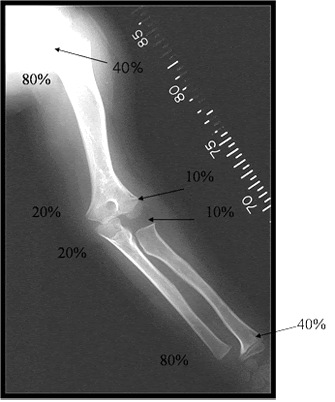

상완골의 경우 근위/원위 : 8:2 비율로

요골의 경우 근위/원위 2.5:7.5 비율로

척골의 경우 근위/원위 2:8 비율로 성장하게 됩니다.

(어깨관절이나, 완관절에서 길이성장이 많이 일어납니다.)

상지 전체로 보았을 때 총100% 기준 상완골 근위 40%/상완골 원위10%/요골 근위 10%/요골 원위 40% 로

상완골과 전완부의 골의 성장이 비등비등하다는 것을 알 수있습니다.